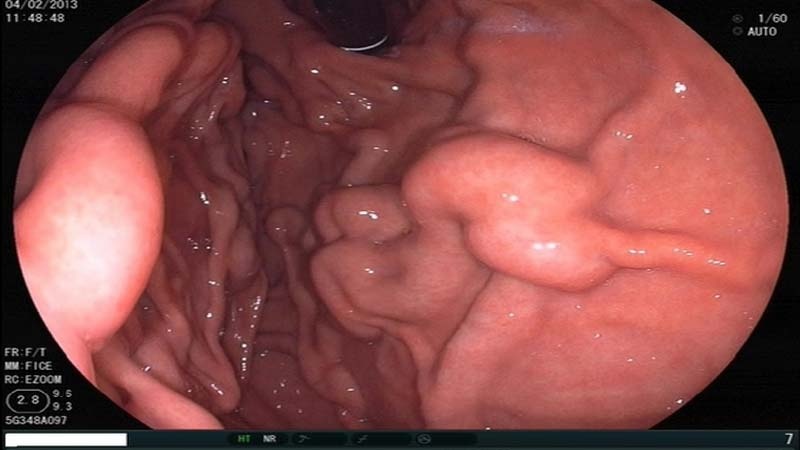

Yemek borusu kanseri sorun yaşayan hücrelerin türüne göre farklı türlere de ayrılır. Yemek borusu kanser türüne teşhis koymak için farklı yöntemler mevcuttur. Yemek borusu kanserine teşhis koyulduğu an doktor kanserin hangi aşamada olduğunu belirlemeli ve böylece uygun tedavi yöntemini seçmelidir. Endoskopi, ultason, bilgisayar yardımı ile tarama ve pozitronlu tomografi yemek borusu kanserinin teşhisi için kullanılır.

Endoskopi, örnek doku alma, cerrahi, kemoterapi, radyoterapi ve ilaçlar, testlere baş vurma da yemek borusu kanserinin teşhisi ve tedavisi için belli başlı yöntemlerdir. Ayrıca tamamlayıcı tıbbi yöntemler sayılan akupunktur ve masaj gibi yöntemlere da baş vurulabilir.

Bu hastalığa teşhis koymak için endoskopi, tomografi ve kapsüllü endoskopi gibi yöntemlere baş vurulur. Kapsüllü endoskopi yönteminde hasta ufak bir kamera taşıyan vitamin şeklinde olan bir kapsülü yutar.

Yemek borusu hastalıklarında da görüldüğü gibi farklı tedavi yöntemlerin söz konusu olduğunu gördük. Yemek borusunun üst bölümünün endoskopisinin yapılması, yemek borusu pH değerinin ölçülmesi, Baryum yutma yöntemi bu hastalıkları teşhisinde kullanılan yaygın yöntemlerdendir. Tedavi için ise doktorlar H2 ilacını, proton pompa inhibitörü gibi ilaçları reçete ederler.

Ayrıca kimi başka yöntemlere baş vurarak da bu hastalık tedavi edilmeye çalışılır. Yemek borusunun özel bir balon yardımı ile genişletilmesi bu yöntemlerden biridir. Bir başka yöntem de endoskopi sırasında yemek borusu varislerinin özel bantlar ile çevrilmesidir. Bu durum varisli damarların bantlar ile sarılmasına ve kanama riskinin azaltılmasına yol açar. Biyopsi veya örnek doku almak da bir başka yöntemdir.